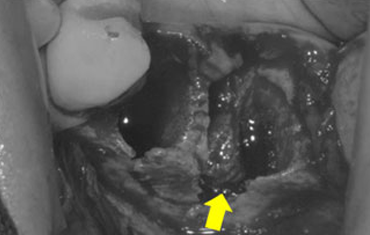

뼈의 소실량이 많은 경우

윗턱뼈 공기주머니에 뼈이식